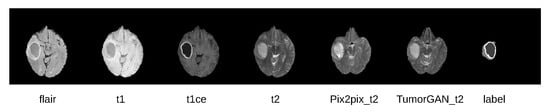

4.3. Qualitative Evaluation